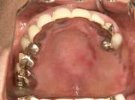

50代女性

歯がこのままではダメだと思い、一念発起された50代女性の方です。

もちろん治療期間が長期にかかることも、治療費が高額になることも、外科的な手術が何度か必要であることなど、

インプラント治療と咬み合わせ治療のほぼ全てを大名歯科ホームページで予め知っていただいた上で決心され来院されたそうです。

インプラント治療は顎骨が乏しかったため、増骨手術も併用しなければならない難症例でした。

治療期間中は残存歯数が少ない上に、丈夫でないため生活に不自由な点がでました。

さらに咬み合わせが安定しにくい症例のため、プラスチック仮歯がよく壊れたり、外れたりして、修理に来院していただくなど大変な苦労とご迷惑をおかけしました。

審美性(見た目)は十分回復できたと思っており、患者さんも大変満足されています。

食事は当然のことかもしれませんが、よく咬めるようになったそうです。

咬み合わせ治療は非常に難しいため、これで十分かどうか分かりませんが現在もこのまま定期的なメインテナンス中です。